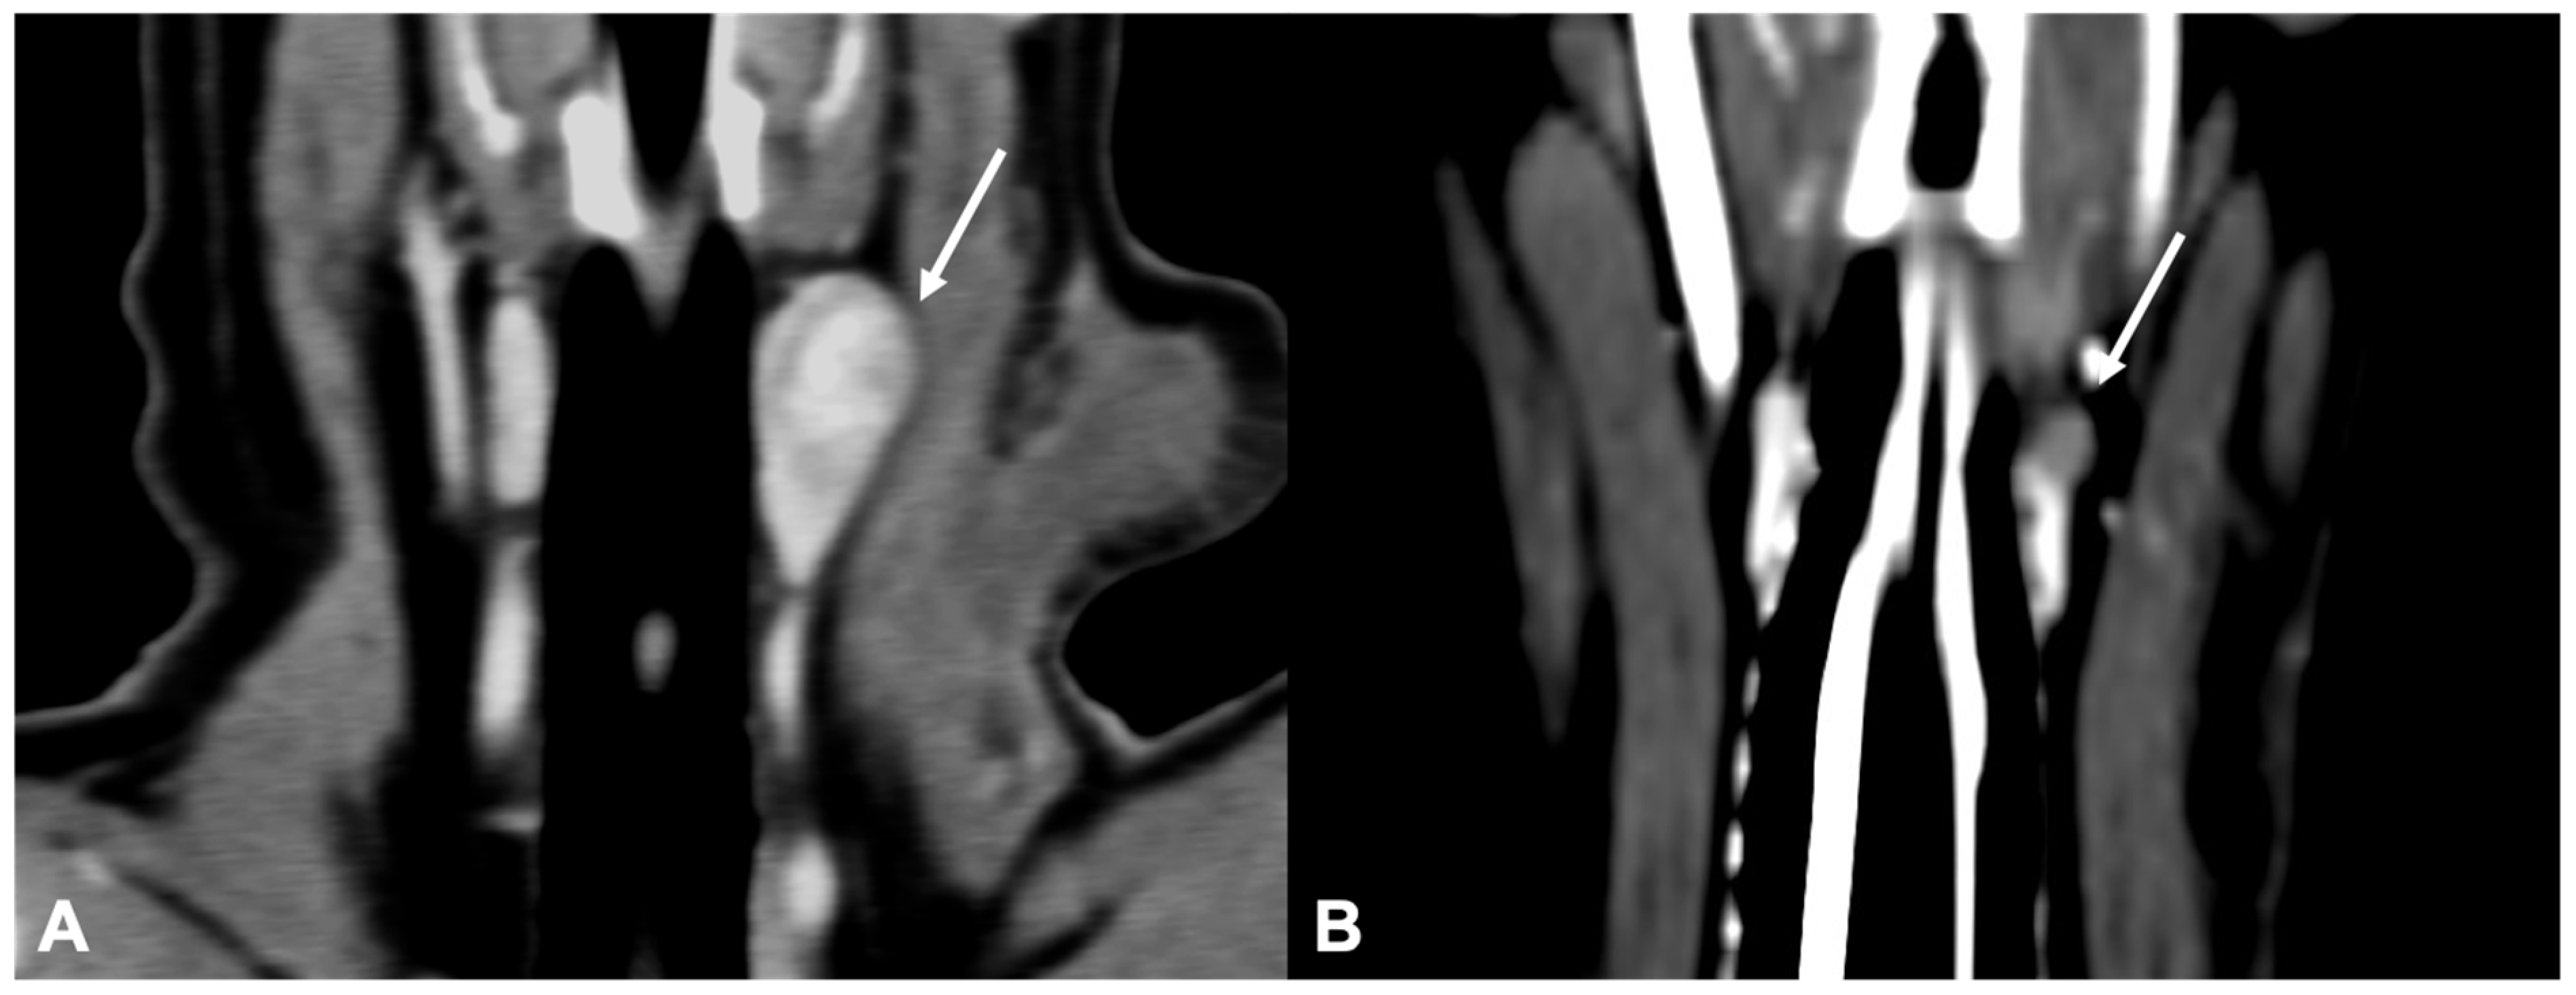

Only two dogs with parathyroid gland hyperplasia (Figure 6) were included in the study; the shape (one rounded and one ovoid) and the contrast enhancement (one homogeneous and one heterogeneous) were variable.

Figure 6.

CT appearance of parathyroid gland hyperplasia. Post-contrast dorsal (A) and right parasagittal (B) CT reconstruction of one dog with parathyroid gland hyperplasia (arrow) at the level of the right internal parathyroid. The parathyroid is ovoid-shaped and homogeneously contrast-enhancing. Note the marked difference in attenuation between the parathyroid (hypoattenuating) and the adjacent thyroid tissue.